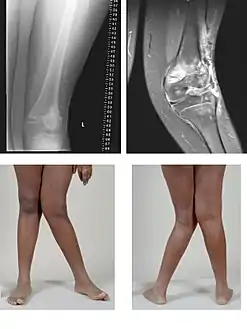

صور إضافية

تَشَوُّهٌ أَرْوَح

(Valgus deformity).

يُلاحظ تزوّي (ميلان) الساق للخارج بعد مفصل الركبة.

صورتان ومقطعان بالرنين المغناطيسي MRI.